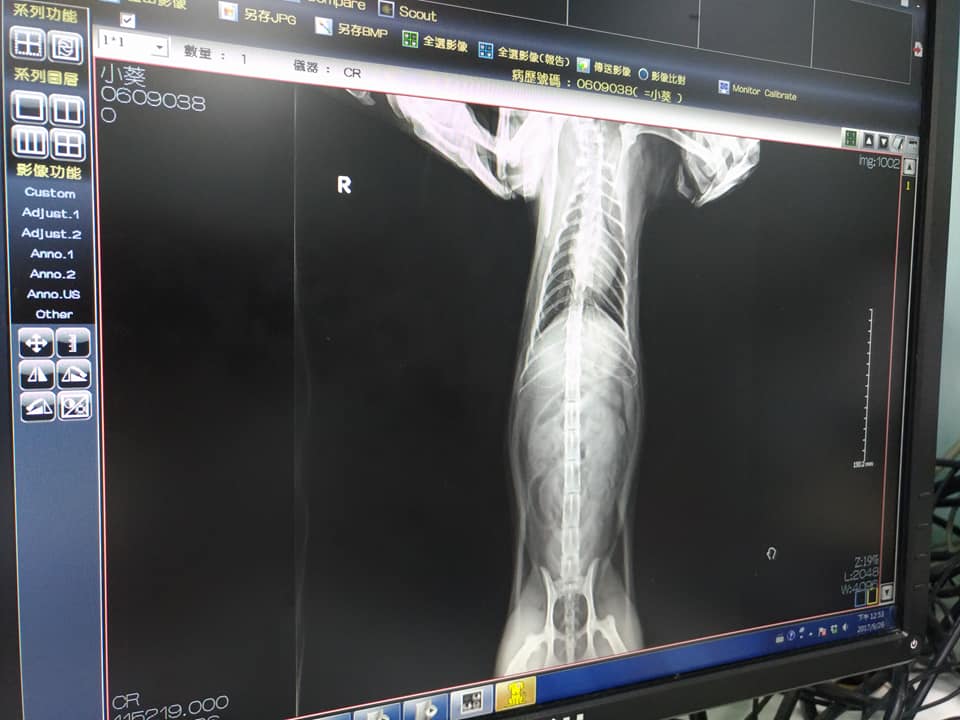

9/26沐恩初診 小葵 3.6KG(跟年初比是瘦了)

口炎嚴重,前小牙都已鬆動,犬齒牙齦痿縮,無疝氣,X光也無大礙。在醫院有流口水的現象。呼吸聲比較大,可能是鼻腔跟喉頭比較窄的關係,鼻腔的X光,必須要鎮靜才能做。